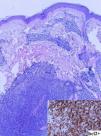

In March 2007, the patient was referred to the dermatology department due to the gradual appearance of asymptomatic subcutaneous nodular lesions on the face, chest and back. The nodules had an erythematous-violacious appearance, were slightly raised, and had diameters ranging between 8mm and 20mm (Fig. 1). Biopsy of the lesions showed a lymphoid infiltrate composed of small monomorphous cells, compatible with FL infiltration (CD20+, Bcl2+, Bcl6+) (Fig. 2). Reassessment of the disease at this time also demonstrated the development of lymphadenopathy, for which chemotherapy was started with a rituximab-CHOP schedule (cyclophosphamide, vincristine, adriamycin and prednisone). Complete remission was achieved after 6 cycles, with clearance of the subcutaneous nodules and the enlarged lymph nodes; subsequently, the patient was placed on maintenance therapy with rituximab administered every 3 months. In December 2009, the patient again presented with cutaneous lesions, predominantly facial, similar to those previously described; biopsy reconfirmed the diagnosis of infiltration by FL. The rituximab maintenance treatment ended in June 2010; the skin lesions were still stable and there was no evidence of disease spread to other areas (peripheral blood immunophenotyping and cervical-thoracic-abdomen CT scan were normal).